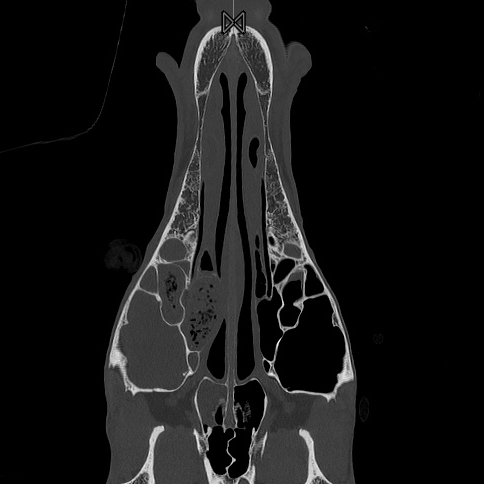

Zur Diagnosestellung wird eine Endoskopie der oberen Atemwege und Nasengänge durchgeführt. Röntgenaufnahmen des Kopfes helfen, einen eventuellen Flüssigkeitsspiegel in den Nebenhöhlen sichtbar zu machen. Eine gründliche Untersuchung der Maulhöhle dient dazu, einen erkrankten Zahn zu identifizieren, der zu den Symptomen passt. Zudem wird ein Röntgen der Zahnwurzeln durchgeführt. Das beste diagnostische Verfahren ist jedoch die Computertomografie (CT), die einen vollständigen, minimalinvasiven Scan des gesamten Kopfes ermöglicht. So können Zahnwurzeln klar abgegrenzt und beurteilt werden, was besonders dann hilfreich ist, wenn bei der Maulhöhlenuntersuchung keine oder nur minimale Befunde vorliegen.